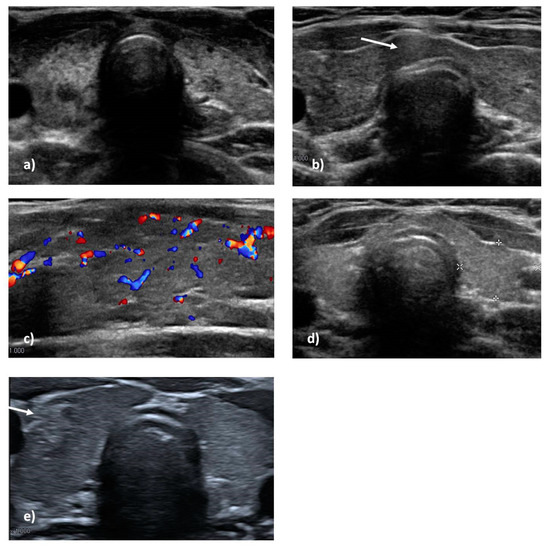

3.1. Thyroid Ultrasound Scan

For each patient, thyroid structural features were collected, and signs compatible with ATD were looked for. Tridimensional measures of thyroid lobes were used to calculate the thyroid lobes’ volume and the total volume. Values were normalized for body surface and height [17,18]. As mentioned, we found thyroid hypoplasia in 6/16 patients with ATD; the left lobe was smaller than the right lobe in 9/16 patients (mean value −0.57 mL); left lobe hypoplasia persisted in 8/16 patients in further ultrasound scan controls (Figure 1). These features were also found in patients affected by 22q11.2DS without ATD. No statistical differences were found between the two groups. However, morphologic anomalies, such as hypoplastic isthmus or lumpy appearance, were described more frequently in patients with progressive ATD (7/16 v. 7/42); this difference was statistically significant (p 0.0096). The only patient with GD developed thyroid cancer a few months after diagnosis and shortly after starting adequate therapy.

Among patients who developed ATD, at the first altered ultrasound scan, the most frequent anomalies suggestive of thyroiditis were inhomogeneous echotexture (13/16), diffuse or irregular hypo-echogenicity (10/16), and vascular overflow (9/16) (Figure 1 and Table 3). Four patients had a pseudo-nodular pattern, and two of these had a hypo-echoic nodule. In all, 12/16 patients also had reactive submandibular or cervical lymphadenopathies; interestingly, 4/16 patients had peri-thyroidal lymphadenopathies. After a first altered ultrasound, and even after beginning therapy, 12/16 patients were subjected to further ultrasound scans, and the anomalies mentioned above persisted over time: inhomogeneous echotexture (11/12), diffuse or irregular hypo-echogenicity (10/12), and vascular overflow (8/12). Reactive parathyroid lymphadenopathies persisted in 4/12 patients, in 3 of whom they persisted even after 3–6 years of therapy (Figure 1 and Table 3).

Among patients who did not develop ATD and who had an ultrasound during follow-up, the most frequent anomalies were inhomogeneous echotexture (14/42) and diffuse or irregular hypo-echogenicity (8/42). Nodules were found in 4/42 patients. Although rare, overflow was described in some patients (2/42), as were parathyroid lymphadenopathies (2/42) (Figure 1 and Table 3). The ultrasound differences between the two groups of patients are shown in Table 3.

Figure 1. Cervical ultrasonography in some patients with 22q11.2 Deletion Syndrome: thyroid gland hypoplasia as well as inhomogeneity, diffuse hypoechoic areas, and pseudonodular pattern (a); diffuse inhomogeneity, hypoechogenity, and perithyroidal lymph node (white arrow) (b). Increased overflow of thyroid lobe on color doppler ultrasonography (c). Left lobe hypoplasia (d); right thyroid lobe neoplasia in a patient with Graves’ disease (white arrow) (e).